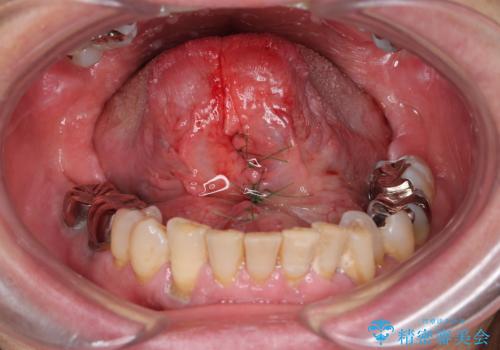

『舌小帯形成術』 ベロの動きを良くして滑舌を改善したい

- 舌の動きが制限され、滑舌を改善したい、と希望され来院されました。

舌小帯形成術を行うことで、滑舌の改善を図ります。形成術は約5分程度で終了し、1週間後に抜糸を行い治療は終了となります。

術後、舌の動きが改善され滑舌の改善を実感することができました。